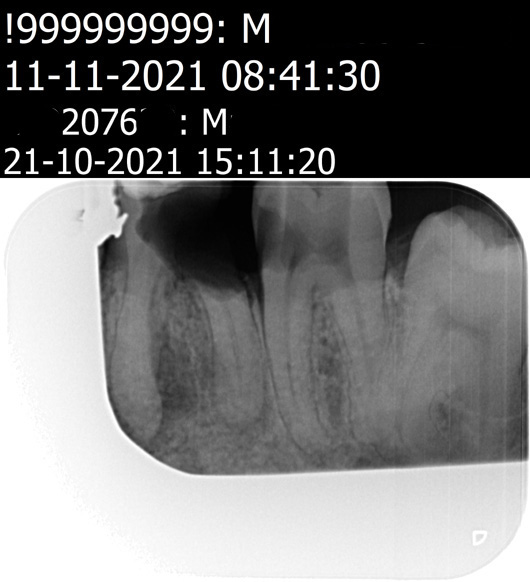

Op de fotos van 12-11-2021 is er volgen tandarts Henk niets bijzonders te zien . Ik zie nu dat er op de fotos van 12-11-2021 geen wortelpunt ontsteking te zien is dat kan . Verder had de tandarts Henk kunnen zien dat er een tijdelijke vulling in zat De wortelkanaalbehandeling niet is afgemaakt

De fotos van 21-10-2021 er is geen begin situatie . Klinische testen zijn er ook niet geweest. Dat er iets met de fotos is geknipt eraan of iets ziet hij ook niet .

foto 1 (21-10-2021) foto2 (21-10-2021) foto3 (12-11-2021) foto 4 (12-11-2021)